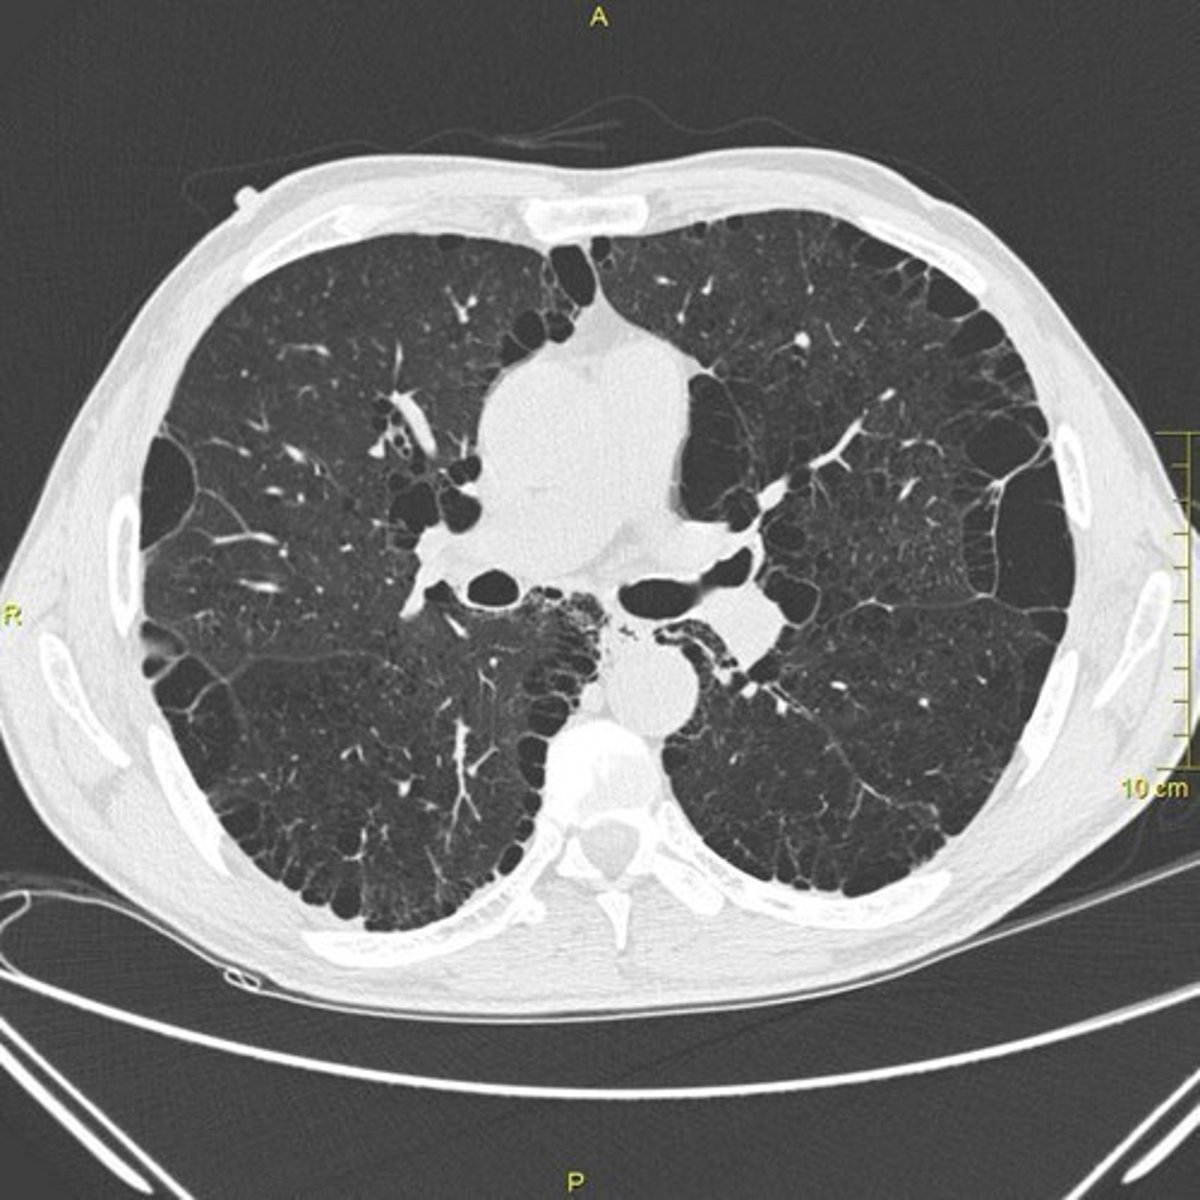

Chronic Obstructive Pulmonary Disease (COPD)

Cause: Long-term smoking, air pollution, genetic factors (e.g., α1-antitrypsin deficiency). ECM Destruction: Elastin and collagen degradation in alveolar walls due to elastase overactivity, leading to emphysema and airway collapse.

Pulmonary Fibrosis (Idiopathic Pulmonary Fibrosis, IPF)

Cause: Chronic lung injury (environmental toxins, infections, acid reflux). ECM Overproduction: Excessive deposition of collagen (Type I and III) and fibronectin by activated fibroblasts (myofibroblasts), leading to stiffened lung tissue.

Pulmonary Fibrosis

Example where excessive collagen deposition stiffens lung ECM, leading to respiratory failure.